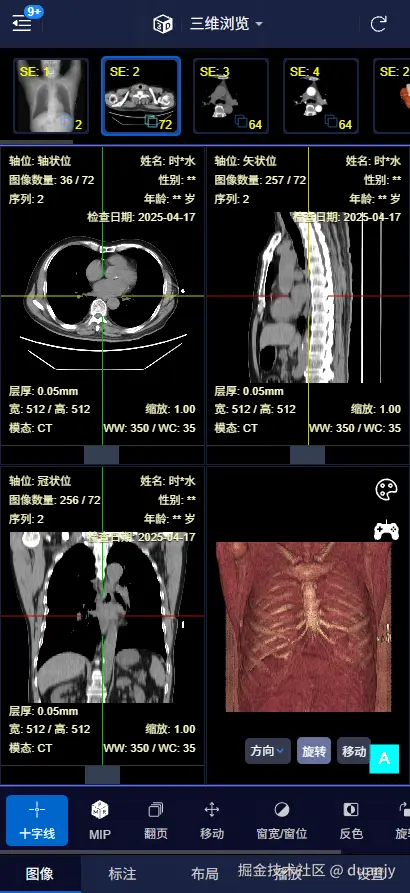

1. 手机端 – 三维重建

mobile-3d.png

支持在 PC 和手机端 打开,可以查看 二维平片三维重建